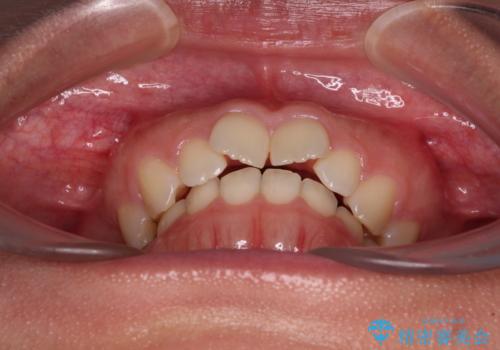

- 上の前歯が前方に飛び出していることを気にして来院された患者様です。

奥歯の咬み合わせをチェックすると、上顎歯列が相対的に前方に位置しているため、補助装置を用いて上顎歯列を確実に後方に移動させ、インビザラインで歯列を整えて行くこととしました。